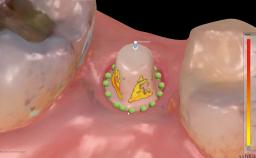

This case from Amélie Mainjot and France Lambert shows how the choice of a screw-retained restoration—which allows adjustment of the profile design over time—was key to managing complications successfully. The authors’ strategic approach avoided a crown remake while also compensating for a soft tissue mismatch. A healthy 20-year-old woman, a non-smoker, presented at the emergency department of the University Hospital of Liège in February 2011 with multiple vertical fractures of tooth 21, incisal fractures of tooth 31, and an enamel and dentin fracture of tooth 32. No tooth luxation was observed. Radiographs confirmed multiple root fractures on tooth 21, including a vertical infrabony fracture, indicating that the tooth was not restorable. A pulpectomy of tooth 21 and an indirect pulp cap on tooth 32 using resin-modified glass-ionomer cement (RMGIC) (Vitrebond; 3M, St. Paul, MN, USA) were performed. RMGC (Fuji IILC; GC, Tokyo, Japan) provisional restorations were placed on the injured teeth. The patient was sent for 3D imaging (multislice CT) the next day to determine the replacement strategy for tooth 21. Because of the vertical fractures, it was important to extract tooth 21 within a few days after the trauma to limit the risk of bacterial infection and consequent tissue loss.